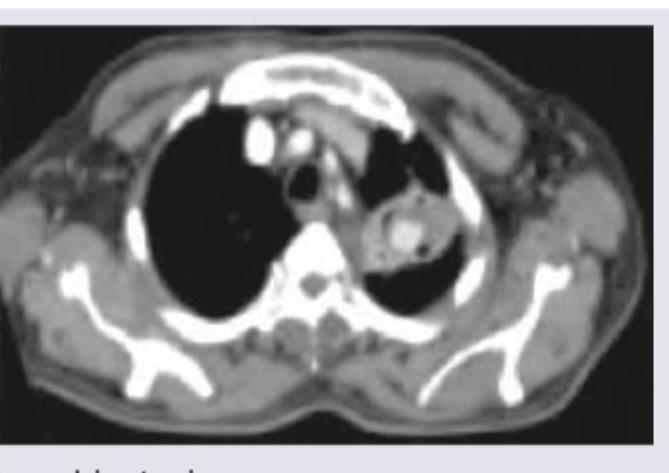

Explanation: ***_Cavity_*** - The CT image clearly shows a complex lesion with a **thick, irregular wall** and a **gas-fluid level** within the lung parenchyma, which is characteristic of a cavity. - The patient's symptoms of **cough, fever, and weight loss over two months**, especially in a diabetic individual, are highly suggestive of a *chronic cavitating pulmonary process*, such as **pulmonary tuberculosis** or a **necrotizing pneumonia/abscess**. *Bronchiectasis* - Bronchiectasis is characterized by **irreversible dilation of the bronchi**, often seen as "tram tracks" or "signet ring" signs on CT, which are not the predominant finding here. - While patients with bronchiectasis can have cough and recurrent infections, the distinct **cavitation** seen on the image is not a primary feature of bronchiectasis itself. *Chronic bronchitis* - Chronic bronchitis is a clinical diagnosis defined by **chronic productive cough for at least three months a year** for two consecutive years, and is primarily a disease of the airways, not typically associated with focal cavitary lesions on CT scans. - The CT findings of a distinct cavitary lesion are not consistent with the imaging features of chronic bronchitis, which usually show **bronchial wall thickening** and **mucous plugging**. *Consolidation with synpneumonic effusion* - **Consolidation** refers to lung tissue filled with fluid or exudate, appearing as opacification, and **synpneumonic effusion** is pleural fluid accompanying pneumonia. - While these can cause cough and fever, the striking feature in the image is the **central lucency with a distinct wall** indicative of a cavity, rather than homogeneous consolidation or a simple pleural effusion.